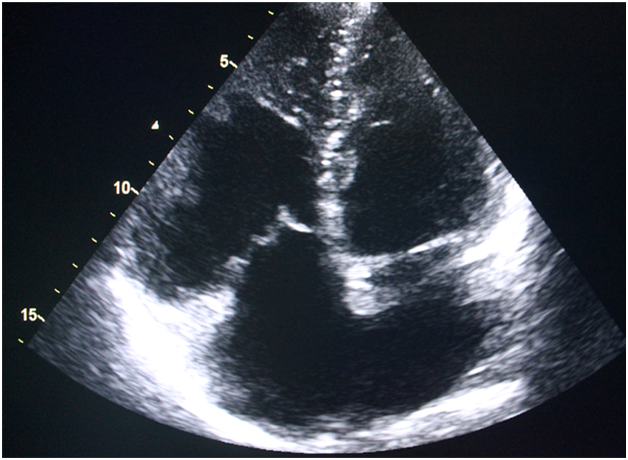

30year male patient was admitted with history of fever and occasional cough for 5months. He was treated in a local hospital for the same with oral and intravenous antibiotics several times but that led to transient symptomatic improvement. On physical examination his axillary temperature was 99degree F, chest was bilaterally clear and cardiovascular system examination revealed loud S2 with fixed split and ejection systolic murmer in pulmonary area. Routine blood test revealed total count 20000/cmm, 71% neutrophil, ESR 91mm,CRP was positive (titre>0.6mg/dl). Liver function test and renal function test were eithin normal limit. Blood culture sent was sterile after 48hours and 7days aerobic/anaerobic incubaton. Chest x ray showed few cavitary lesion following which CT scan thorax was done that revealed multiple thin walled cavitary lesion suggestive of sequelae of old infection. 2D echocardiography showed OS-ASD of 18mm with left to right shunt and mobile vegetation was seen on pulmonary valve. Patient was started on intravenous ceftriaxone and gentamycin. Subsequent echocardiography during hospitalization showed only mild to moderate pulmonary regurgitation and moderate pulmonary hypertension along with the previous findings. The patient had no other clinical manifestation, or identifiable complication including thromboembolism. CRP was negative after completion of antibiotics. The patient was discharged after 6 weeks in stable condition. Nevertheless the pre discharge echocardiography revealed persistence of vegetation, which had developed a fibrotic appearance and persistent mild to moderate pulmonary regurgitation.

Right-sided infective endocarditis (RSIE) is a rare condition constituting 10% of cases of Infective Endocarditis.1 Infective endocarditis (IE) involves the aortic valve as the most common followed by the mitral valve as more common. Tricuspid and pulmonary valve are the least commonly involved. In patients with congenital heart defects, left, right and both sided IE accounts for 46.4%, 32.7% and 2.3%, respectively.2 Prevalence of isolated tricuspid and pulmonary valve IE is 2.5-3.1% and 2%, respectively.3,4 It is usually seen to be associated with intravenous illicit drug use (IVDU) or central catheter use. Staphylococcus aureus is the most common infectious agent in all cases.5 Most cases of right sided infective endocarditis involves the tricuspid valve. Incidence of RSIE is on the rise due to increase number of patients using central venous lines, as well as pacing and other intravascular devices.6 It is also commonly seen in patients on maintenance hemodialysis. Infective endocarditis involving the pulmonic valve is extremely rare, accounting for only 1.5 to 2.0% of hospital admissions for infective endocarditis.7 IE may be isolated to the pulmonic valve alone or it may concomitantly affect other valves. Both structurally normal and heart with abnormal valves have been associated with pulmonic valve endocarditis. Low incidence of infection on the pulmonic valve compared with other cardiac valves can be explained relating to differences in hemodynamic pressures across the valves, oxygen saturation, underlying congenital or acquired valvular abnormalities. The endothelial lining and relative vascularity of the valves has also significant role. Clinical manifestation of pulmonic valve endocarditis is similar to that of tricuspid valve infection. Fever, breathing difficulty, pleuritic chest pain are the predominant symptoms. Radiographic and laboratory evidence frequently corroborates the presence of pulmonary embolism. Approximately one half of patients will have pulmonic regurgitant murmur present on cardiovascular examination. Due of the nonspecificity of symptoms and lack of peripheral stigmas typically associated with mitral or aortic valve involvement, the diagnosis of pulmonic valve endocarditis usually takes time. It may be delayed for up to 6months. A high index of suspicion is needed to diagnose a case of pulmonary valve endocarditis for better management and outcome. Interatrial communication has been reported in some cases of RSIE, however, these involved normal native pulmonary valves.8 Pulmonary valve IE associated with ASD has rarely been reported in literature. To conclude, in presence of longstanding fever with non specific symptoms a proper assessment of pulmonary valve should be done with TTE and also TEE if possible. Other clinical conditions should be corroborated also specially in situations when a patient is having predisposing heart disease. A high clinical index of suspicion with proper diagnostic method will help in diagnosing and proper management (Figure 1) (Figure 2).

Figure 2Transthoracic echocardiography apical four chamber view showing ostium secundum atrial septal defect.